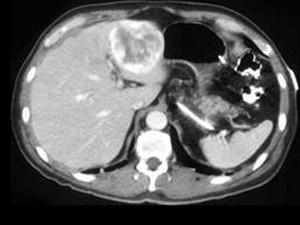

问题 男,40岁,中上腹胀疼不适,CT扫描如图,最佳的诊断为 ( )

选项 A、肝血管瘤 B、肝血管内皮瘤 C、胆管细胞癌 D、肝转移瘤 E、原发性肝癌

答案 A